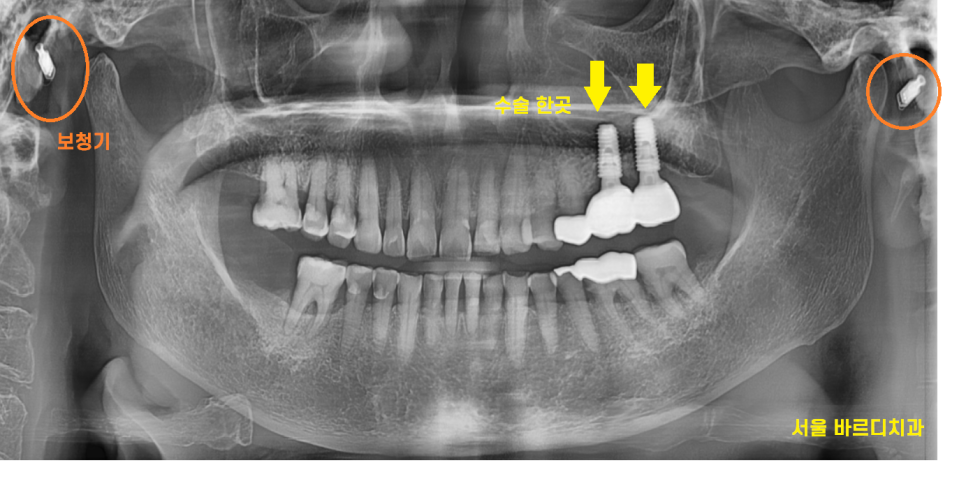

23.10.30

고덕동 치과 수술 결과입니다.

아주 예쁘게 심어졌습니다.ㅎㅎ

환자분도 고령에 약 드시는것도 있고 하셔서

수술에 대한 부담감을 가지고 계셨습니다.

제가 환자분 구강 상태를 분석하고

수술 예측한 것을 보여드리니까

안심하고 수술받으셨던 기억이 납니다.

24.04.16

보청기를 끼셔서 소통이 어려운 부분도 없지 않았지만

글로 쓰고

사진으로 과정 보여드리면서 노력했던 환자분

마무리까지 완성 되었습니다!